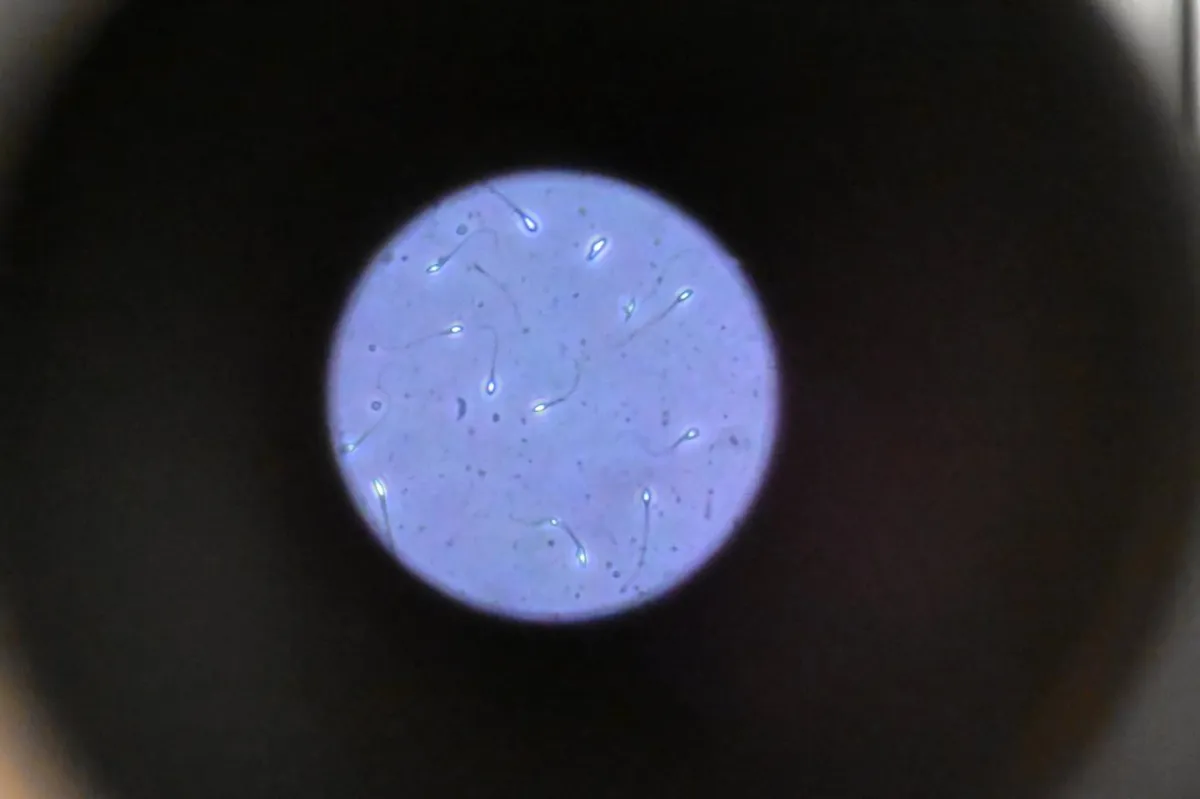

Mikroskopta görülen sperm hücreleri (AFP)

Çinli araştırmacılar, sperm hareketliliğini artıran bir losyon geliştirdi. Bu gelişme, küresel erkek doğurganlığı krizinin çözümüne katkı sağlayabilir.

Erkeklerin doğurganlığı son 50 yıldır dünya çapında düşerken, anormal sperm morfolojisinin yanı sıra hücre sayısı ve hareketliliğinde de azalma yaşanıyor.

Fudan Üniversitesi Üreme ve Gelişim Enstitüsü'nden bilim insanları, sperm kalitesini artırmak için kolay uygulanabilir bir merhem geliştirdi.

Testislere haricen uygulanan losyonu hayvanlar üzerinde test ettiler. Bilim insanları, The Innovation adlı hakemli dergide yayımlanan yeni çalışmada, "Bu rahatsızlığa karşı son derece etkili, hedefe yönelik biyolojik ajanlar gerekli" ifadelerini kullanıyor.

Araştırmacılar erkek fareleri, ısı stresi, yapışmaz plastik kaplama PTFE (politetrafloroetilen) ve kurşun gibi sperm hareketliliğini azalttığı bilinen faktörlere maruz bıraktı.

Sperm kalitesinde düşüş olduğunu doğruladıktan sonra, SKAP2'den yapılan hidrojeli kemirgenlerin testislerinin üzerindeki cilde uyguladılar. SKAP2, normal sperm yapısını ve hareketini koruduğu bilinen bir protein.

Bilim insanları jelin, sütten elde edilen ve SKAP2 proteinini deri yoluyla hücrelere taşıyan güvenli, jöle benzeri parçacıklar kullanılarak yapıldığını söylüyor. Araştırmacılar, SKAP2 proteininin sperm kalitesini onarması veya iyileştirmesi için gereken yere doğrudan ulaşmasını sağlamak amacıyla bu jeli geliştirdi.

Araştırmacılar jeli bir ay boyunca uyguladıktan sonra kemirgenlerin sperm hareketinde büyük iyileşmeler yaşandığını ve çoğu durumda normal seviyelere döndüğünü tespit etti.

Bilim insanları çalışmada, "Erkek üreme sağlığı için yenilikçi bir müdahale sunan bu hidrojel uygulaması önemli bir potansiyele sahip" diye yazıyor.

Losyonun, sperm hareketliliğinin azalmasına karşı "hedefe yönelik ilk onarım stratejisi" olduğunu da ekliyorlar.

Bilim insanları jeli, düşük sperm hareketliliği teşhisi alan erkeklerin menisinde de test etti.

Meni örnekleri jelle kültürlendikten sonra sperm hareketi ve canlılığında kayda değer bir gelişme görüldü.

Bilim insanları, "Bu ajanla ilgili çalışma sonuçları, hedefe yönelik ve isabetli tedavi seçenekleri sunması gibi yönleriyle, klinik rehberlikte büyük önem taşıyor" diyor.

Sperm hareketliliği ve morfolojisini geliştirerek hem doğal döllenme hem de yardımla üremede başarı oranlarını daha da artırabilir.